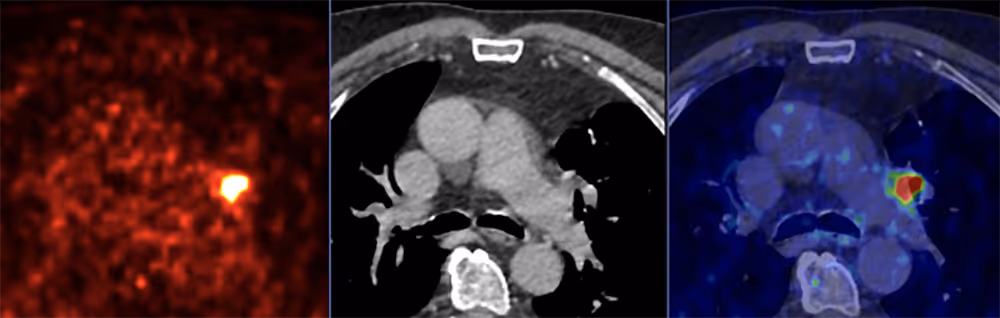

- moderne molekulare Bildgebung wie die PSMA PET/CT, insbesondere bei fortgeschrittenem Stadium oder bei erneut steigendem PSA-Wert

Gerade bei Verdacht auf Metastasen oder bei unklaren Befunden kann die PSMA PET/CT zusätzliche, präzisere Informationen liefern und so die Therapieplanung wesentlich beeinflussen.

- PSMA PET/CT als moderne molekulare Bildgebung zur Detektion auch kleiner oder schwer sichtbarer Metastasen

Insbesondere bei steigenden PSA-Werten nach einer bereits durchgeführten Therapie oder bei Verdacht auf ein fortgeschrittenes Stadium kann die PSMA PET/CT eine präzisere Einschätzung der Tumorverteilung ermöglichen.

Die genaue Erfassung der Metastasen ist zentral, um zu entscheiden, ob eine lokale, systemische oder gezielt molekulare Therapie – etwa eine PSMA Radioligandentherapie – sinnvoll ist.

PSMA Radioligandentherapie – gezielte molekulare Behandlung

Bei fortgeschrittenem oder metastasiertem Prostatakrebs kann eine PSMA Radioligandentherapie eine zusätzliche Behandlungsoption darstellen. Dabei bindet ein radioaktiv markiertes Molekül gezielt an PSMA-exprimierende Tumorzellen und zerstört diese von innen heraus. Voraussetzung ist in der Regel eine ausreichende PSMA-Expression, die zuvor mittels PSMA PET/CT überprüft wird.

Die PSMA PET/CT Diagnostik kann helfen, die tatsächliche Tumorverteilung präzise darzustellen und damit eine fundierte Therapieentscheidung zu ermöglichen. Auf dieser Basis kann – sofern medizinisch geeignet – auch eine PSMA Radioligandentherapie geprüft werden.

Eine PSMA PET/CT kann insbesondere bei unklarer Metastasierung, bei fortgeschrittenem Stadium oder bei erneut steigendem PSA-Wert nach einer Vorbehandlung zusätzliche diagnostische Sicherheit bieten. Sie dient der präzisen Beurteilung der Tumorverteilung und kann die Therapieplanung maßgeblich beeinflussen.